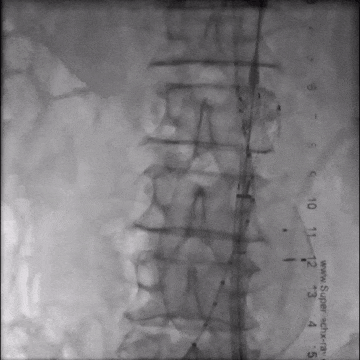

释放短腿(交叉腿)

导丝超选右髂支

右侧延续16-18-140mm髂支

左侧延续16-18-140mm髂支

术中释放右侧髂支后,患者突发腹痛、心率增快、血压下降,造影怀疑右髂动脉破裂,紧急加放髂支并弹簧圈栓塞。

术后患者持续腹痛,白细胞、肌酐、D-二聚体进行性升高。